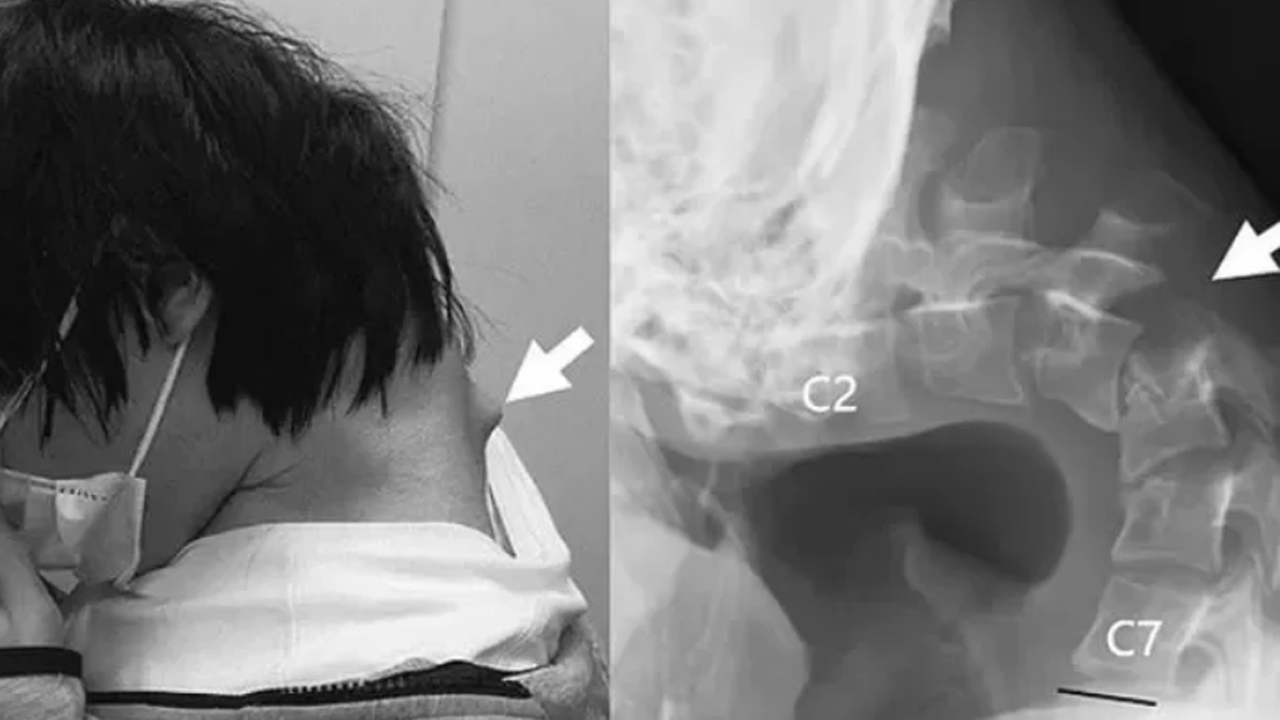

A páciensnél – aki megállás nélkül a telefonján játszott – egy nagy dudor alakult ki a nyaka hátsó részén, és már nem tudta felemelni a fejét a nyakizmaival. Mielőtt orvosi segítséget kért volna, súlyos nyakfájdalmakat tapasztalt, sőt nehezen tudta az ételt lenyelni, ami gyors súlycsökkenéshez vezetett. Végül a nyaka olyan gyenge lett a természetellenes pozíció miatt, hogy már nem tudta felemelni a fejét.

Teljesen eltorzult a a nyaka attól, hogy állandóan lehajtott fejjel bámulta a mobilját – Forrás: odditycentral.com

A vizsgálatok kimutatták, hogy a nyaki csigolyái eltorzultak és elmozdultak, valamint hegszövet alakult ki a felső gerincén, mivel hosszú időn keresztül „rendkívül megnyúlt” állapotban volt. Kezdetben az orvosok nyakmerevítőkkel próbálták kezelni a lecsüngő fejet, de miután a páciens zsibbadásra panaszkodott a nyakában, más megoldás mellett döntöttek. Több műtéti eljárás során eltávolították az eltorzult csigolyák egy kis részét és a hegszövetet, majd csavarokat és fémrudakat helyeztek be a nyakcsontjaiba, hogy korrigálják a testtartását.